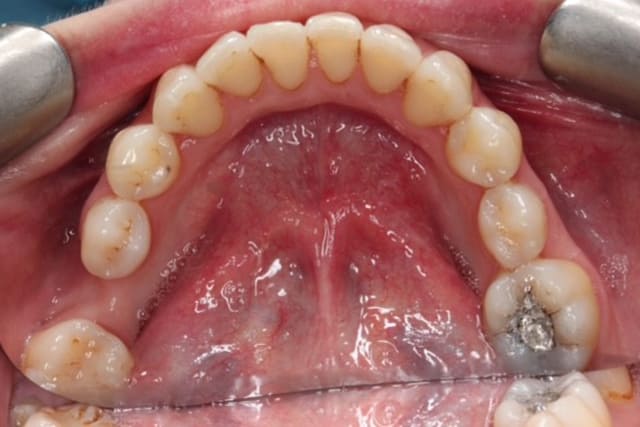

Regular visits to a dental hygienist will help improve your dental health and prevent periodontal (gum) disease, bleeding gums and dental decay (caries).